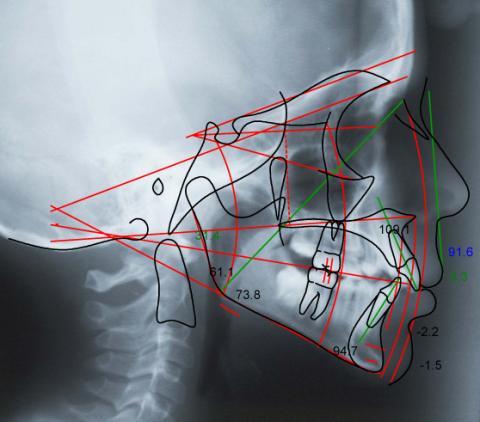

1. Radiographic information (FMX, Panorex, Cephalogram, Tomograms)